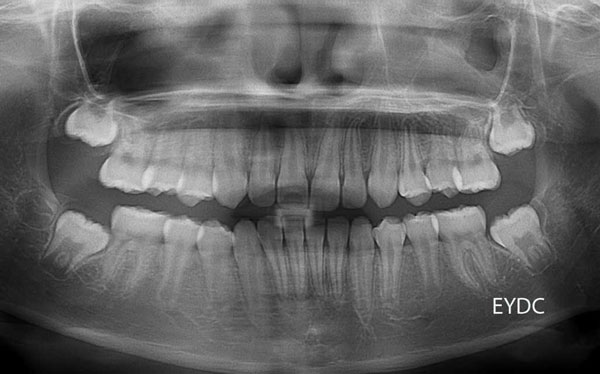

被曝量のきわめて少ないデジタルレントゲンで、歯の生える状況を定期的に観察していきます。とてもきれいに並んできました。11才7ヶ月。